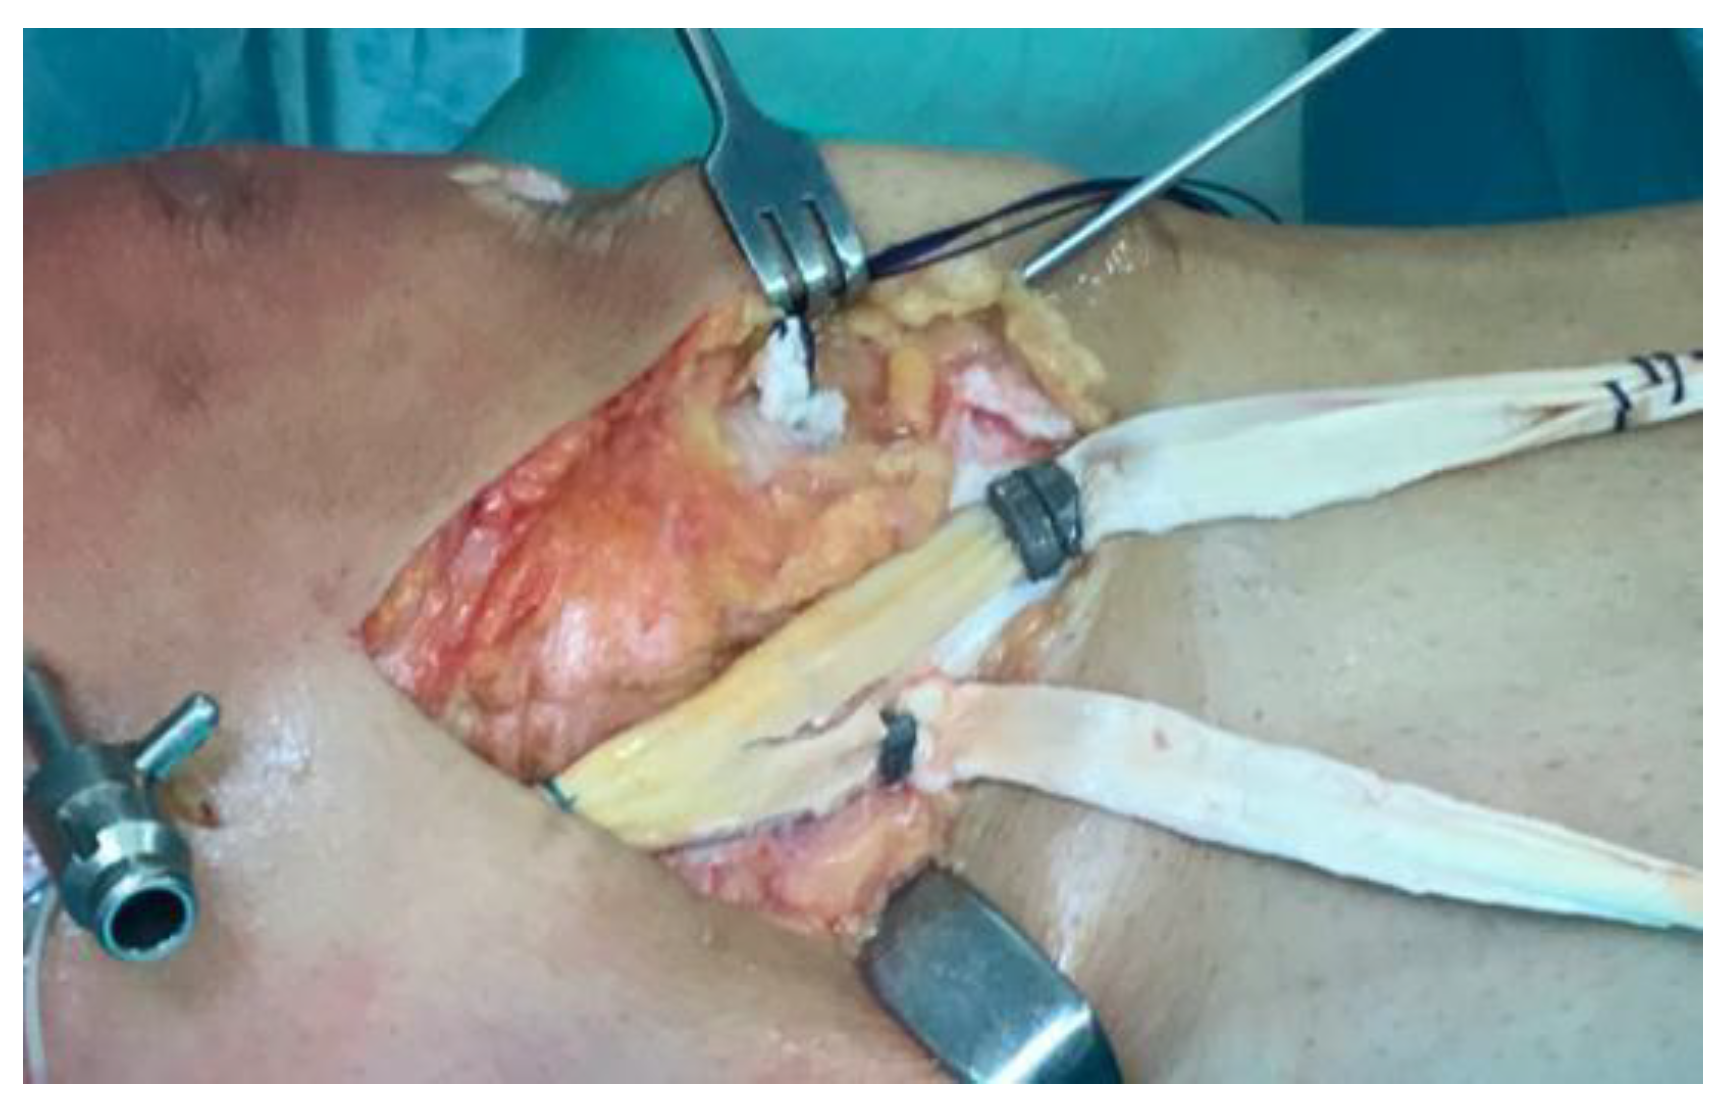

- Direct repair: reattaching the MCL using screws and washers or a suture anchor [4].

- Lind (Danish) reconstruction: a semi-anatomic “double-bundle” reconstruction of the sMCL and POL. The patient’s semitendinosus autograft is harvested, preserving the tibial insertion, and is fixed proximally at the sMCL insertion to recreate the sMCL and distally on the tibia to mimic the POL. This method does not aim for exact replication of ligament insertions but reconstructs two structures with a single autograft and uses only one femoral tunnel [8].

- Hughston reconstruction: focuses on capsular and POL “plication” to restore natural soft-tissue tension. It leverages anatomical features of the posteromedial corner, notably the proximal portion of the sMCL, which has significant soft-tissue adhesions to the medial femoral condyle that can help disperse tension. It is valued for simplicity and cost-effectiveness [54].

- New reconstruction option: the latest “triple-stranded” MCL reconstruction uses three different grafts aimed at recreating the sMCL, POL, and dMCL [55].